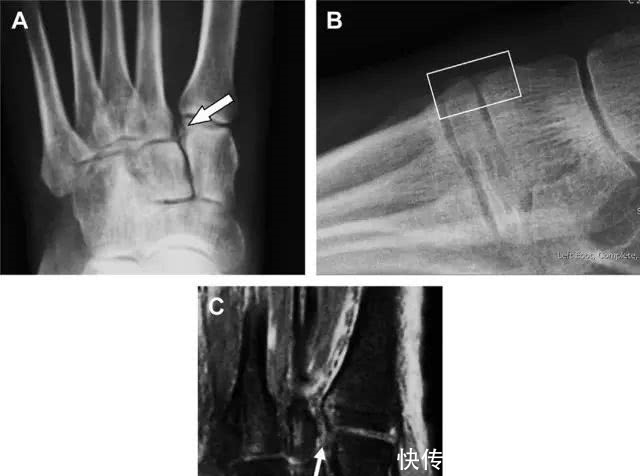

与跗跖关节韧带相关的骨折常由旋前或旋后的跖屈损伤引起。尽管跗跖关节骨折脱位仅占所有骨折的 0.2%,但是约 20% 的这些骨折在初次检查时被漏诊。初次 X 片可能示正常,但是负重位 X 线片常常提示脱位或半脱位。

典型表现:第二跖骨底和内侧楔骨之间的骨折碎片,跖骨间间隙增宽(图 8)。脱位亦可发生在舟骨-内侧楔骨关节,导致另一种变异的跗跖关节损伤(图 9A)。此外,骰骨的小块皮质撕脱在足部斜位片上可清晰显示(图 9B)。

图 8 从马上摔落的患者,跗跖关节骨折。A 正位片示内侧楔骨旁边的小骨折碎片(箭头),第二跖骨底向外半脱位;B 负重位侧位片示第二跖骨相对中间楔骨向背侧轻微移位(长方形);C STIR 序列 MRI 图像示跗跖关节韧带断裂(箭头),第一至第三跖骨、内侧楔骨及中间楔骨均骨髓水肿

图 9 变异的跗跖关节骨折。A 另一种类型的跗跖关节损伤,中间楔骨向内侧半脱位(弧形箭头),从而使第一、第二跖骨间间隙变宽,需注意,骨折在靠近内侧楔骨处(箭头);B 外侧跗跖关节损伤伴随从骰骨跖骨韧带的骰骨撕脱(箭头),需注意,第五跖骨底近端处存在软组织水肿(空箭头)